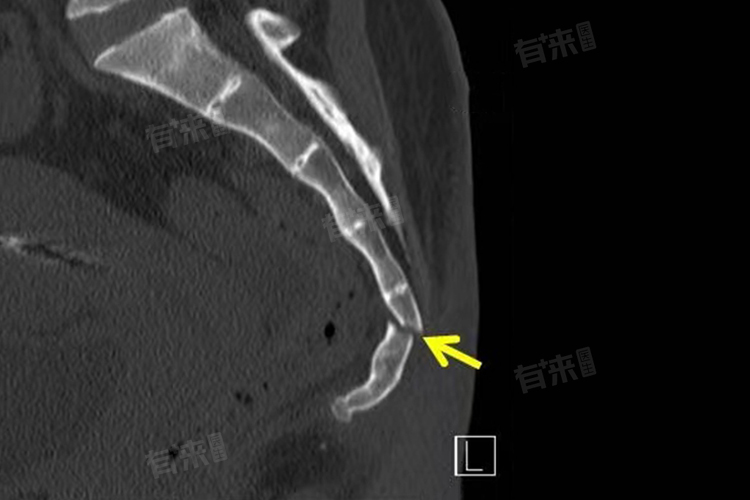

S5椎体骨折问题是否严重不能一概而论,需要综合多方面因素来判断,轻者可保守恢复,问题不大,重者损伤神经、软组织等,问题较大。

- 然而,若骨折情况较为复杂,问题就可能比较大。一方面,当骨折断端移位明显时,可能会损伤周围的神经,尤其是骶神经。骶神经负责控制盆底肌肉、肛门括约肌以及会阴部的感觉等,一旦受损,患者可能出现大小便失禁、性功能障碍等严重后果,极大地影响生活质量,后续还需要漫长且复杂的康复治疗,甚至部分功能难以完全恢复如初。

- 另一方面,若骨折合并有严重的软组织损伤,导致局部大量出血,形成血肿,不仅会引发剧烈疼痛,还可能因为血肿压迫周围组织,加重神经、血管损伤风险,处理不及时可能引发感染,出现发热、局部红肿热痛加剧等症状,严重时可发展为骨髓炎,治疗难度大幅增加,病程延长,患者身体和心理都将承受巨大痛苦。